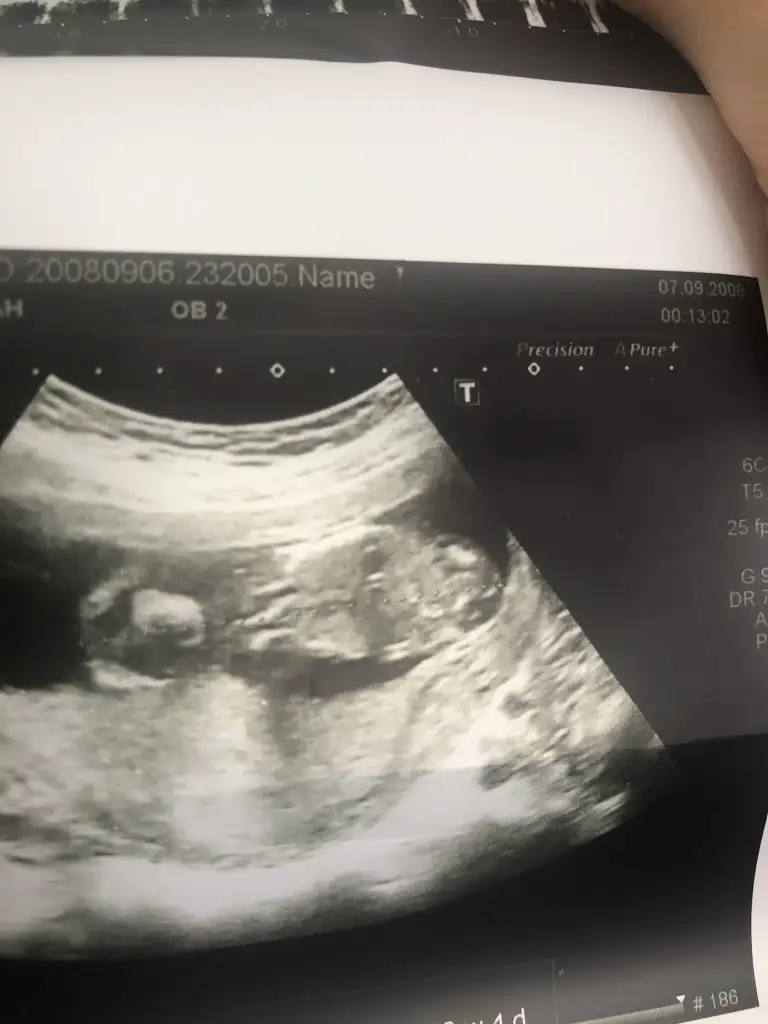

Bu bacak arası evet. Benim de ilk erkek olarak söylemişti doktorum sonra kız oldu. Hala tereddütteyim ben de. Detaylıya kadar bekliyoruz o yüzden :)Ya arkadaşlar bebeğim 16 haftalık bugün 4 lü tarama için gittim 16 hafta boyunca bebeğe erkek diyen doktor bugun de kıza benziyo dedi şaştım kaldım nasıl öğrencem ben cinsiyeti doğru hangisi ? EKLEDİĞİM GÖRSELDE BACAK ARASINI MI ÇEKTİ BİLMİYORUM BAKAR MISINIZ

16 haftaya kadar her gittiğimde erkek çıkıntısı var dediler 16. Haftada kız dedi doktorKız gibi canım bana öyle geldi çünkü erkek de çıkıntı hemen belli oluyor bunda hiç çıkıntı yok ve 16. Haftaya kadar çok çok daha belli olurdu

Ama bacak arasını net görmemiş demekki… keşke net görmüyorsa söylemeseler… yani benim 12 haftada bacak arası boştu ama yandan bakınca vardı çıkıntı… kızda da da erkekte de bu haftalarda olur çıkıntı oyüzden bacak arasını görmek lazım… instagramda mehmet boz’un videolarını bak cinsiyetle ilgili… aslında çok net oluyor her şey…Bebeği 16. Haftaya kadar böyle görerek söyledi dünde dörtlü taramada tek tek vücudunu ölçerken kız dedi ama erkek demiştiniz dedim bak çıkıntısı yok kıza benziyo yani dedi şaşırdı o da erkek mi demişim dedi

Evet bendeCanım bana da kız gibi geldi bebeğimin cinsiyetini çok merak ettiğim için bununla ilgili 1000 tane video izledim, erkek bebekte çıkıntı kız bebekte 3 tane çizgi oluyor böyle yan yana :)

Bu arada senin bebişinde kız benceÜç çizgi falan hiç bahsetmedi sadece bacak arası boş dedi